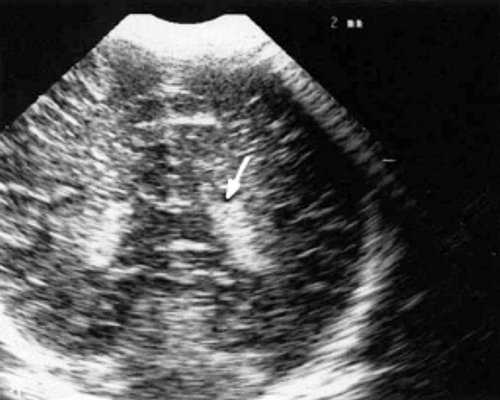

У детей этой группы при первом эхоэнцефалографическом исследовании были выявлены субэпендимально расположенные кистозные структуры на уровне таламо-каудальной вырезки (ТКВ) и (или) кпереди от нее диаметром от 0,3 до 1,1 см. У части новорожденных субэпендимальные кисты были представлены единой полостью с однородным или неоднородным содержимым, у других детей эти структуры напоминали соты, т. е. состояли из множества жидкостных включений, окруженных эхопозитивным ободком (рис. 3). Эти структурные особенности субэпендимальных кист, по-видимому, обусловлены разными стадиями резорбции. У 10 детей субэпендимальные кисты располагались в симметричных участках обоих полушарий, у 2 новорожденных - только в левом полушарии. У 3 детей, помимо субэпендимальных кист, расположенных в таламо-каудальной вырезке и (или) кпереди от нее, дополнительно выявлены субэпендимальные щелевидные кистозные структуры на уровне средних или передних отделов лобных рогов (см. рис. 3).

Рис. 3. Эхоэнцефалограмма ребенка Б. со смешанной герпес-цитомегаловирусной инфекцией, 5-е сут. жизни.

а) Правое полушарие. Стрелками обозначены субэпендимальные кисты, имеющие вид сот, расположенные в таламокаудальной вырезке и кпереди от нее.

б) Левое полушарие. Стрелками обозначены субэпендимальные кисты, имеющие вид сот, расположенные в таламокаудальной вырезке и кпереди от нее.